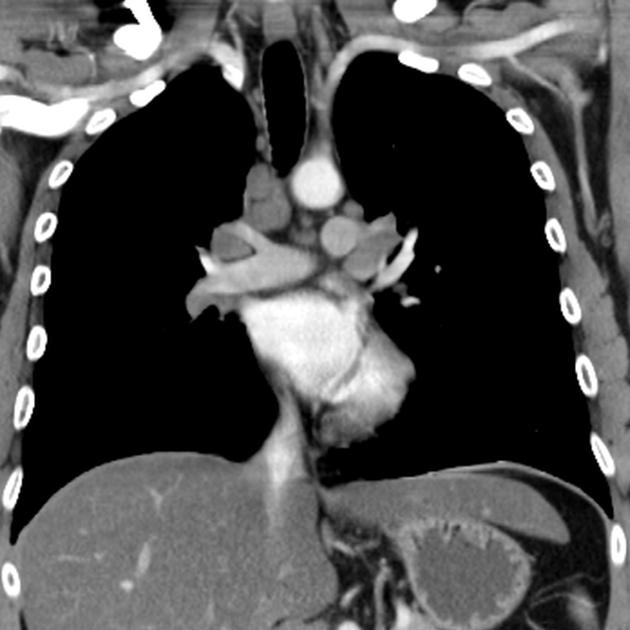

Phình động mạch chủ ngực (Thoracic aortic aneurysm)